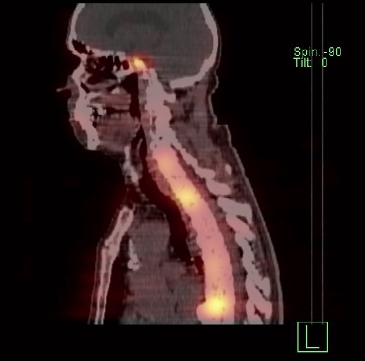

/ Obr. č. 1: Celotělová scintigrafie a SPECT/CT za 4 hod. po aplikaci OctreoScanu.

/ Obr. č. 4: Celotělová scintigrafie a SPECT/CT za 24 hod. po aplikaci OctreoScanu.

Popis: pozorujeme patologicky zvýšenou depozici radiofarmaka:

- v několika fokusech skeletu (nejkontrastněji v proc. spinosus Th10, dále v hrotu pyramidy os temporale vlevo, tělech Th3, Th6, Th8, Th12, L4, kosti kyčelní vlevo), vícečetně v žebrech oboustranně, v ldCT obraze mnohočetná smíšená převážně sklerotická ložiska

- nehomogenní kumulace v játrech, místy až s fokusy, nejnápadnější je v levém laloku ventromediálně

- v ložisku v malé pánvi pararektálně vlevo vel. cca 48x38mm

Akumulace v žlučníku, slezině, levé ledvině, močovém měchýři a střevních kličkách představuje fyziologickou distribuci.

Závěr: Mnohočetná ložiska patologicky zvýšené denzity somatostatinových receptorů, které odpovídají neuroendokrinní nádorové tkáni a generalizaci onemocnění (výrazně skelet, v ložisku v pánvi pararektálně a velmi suspektně v játrech).